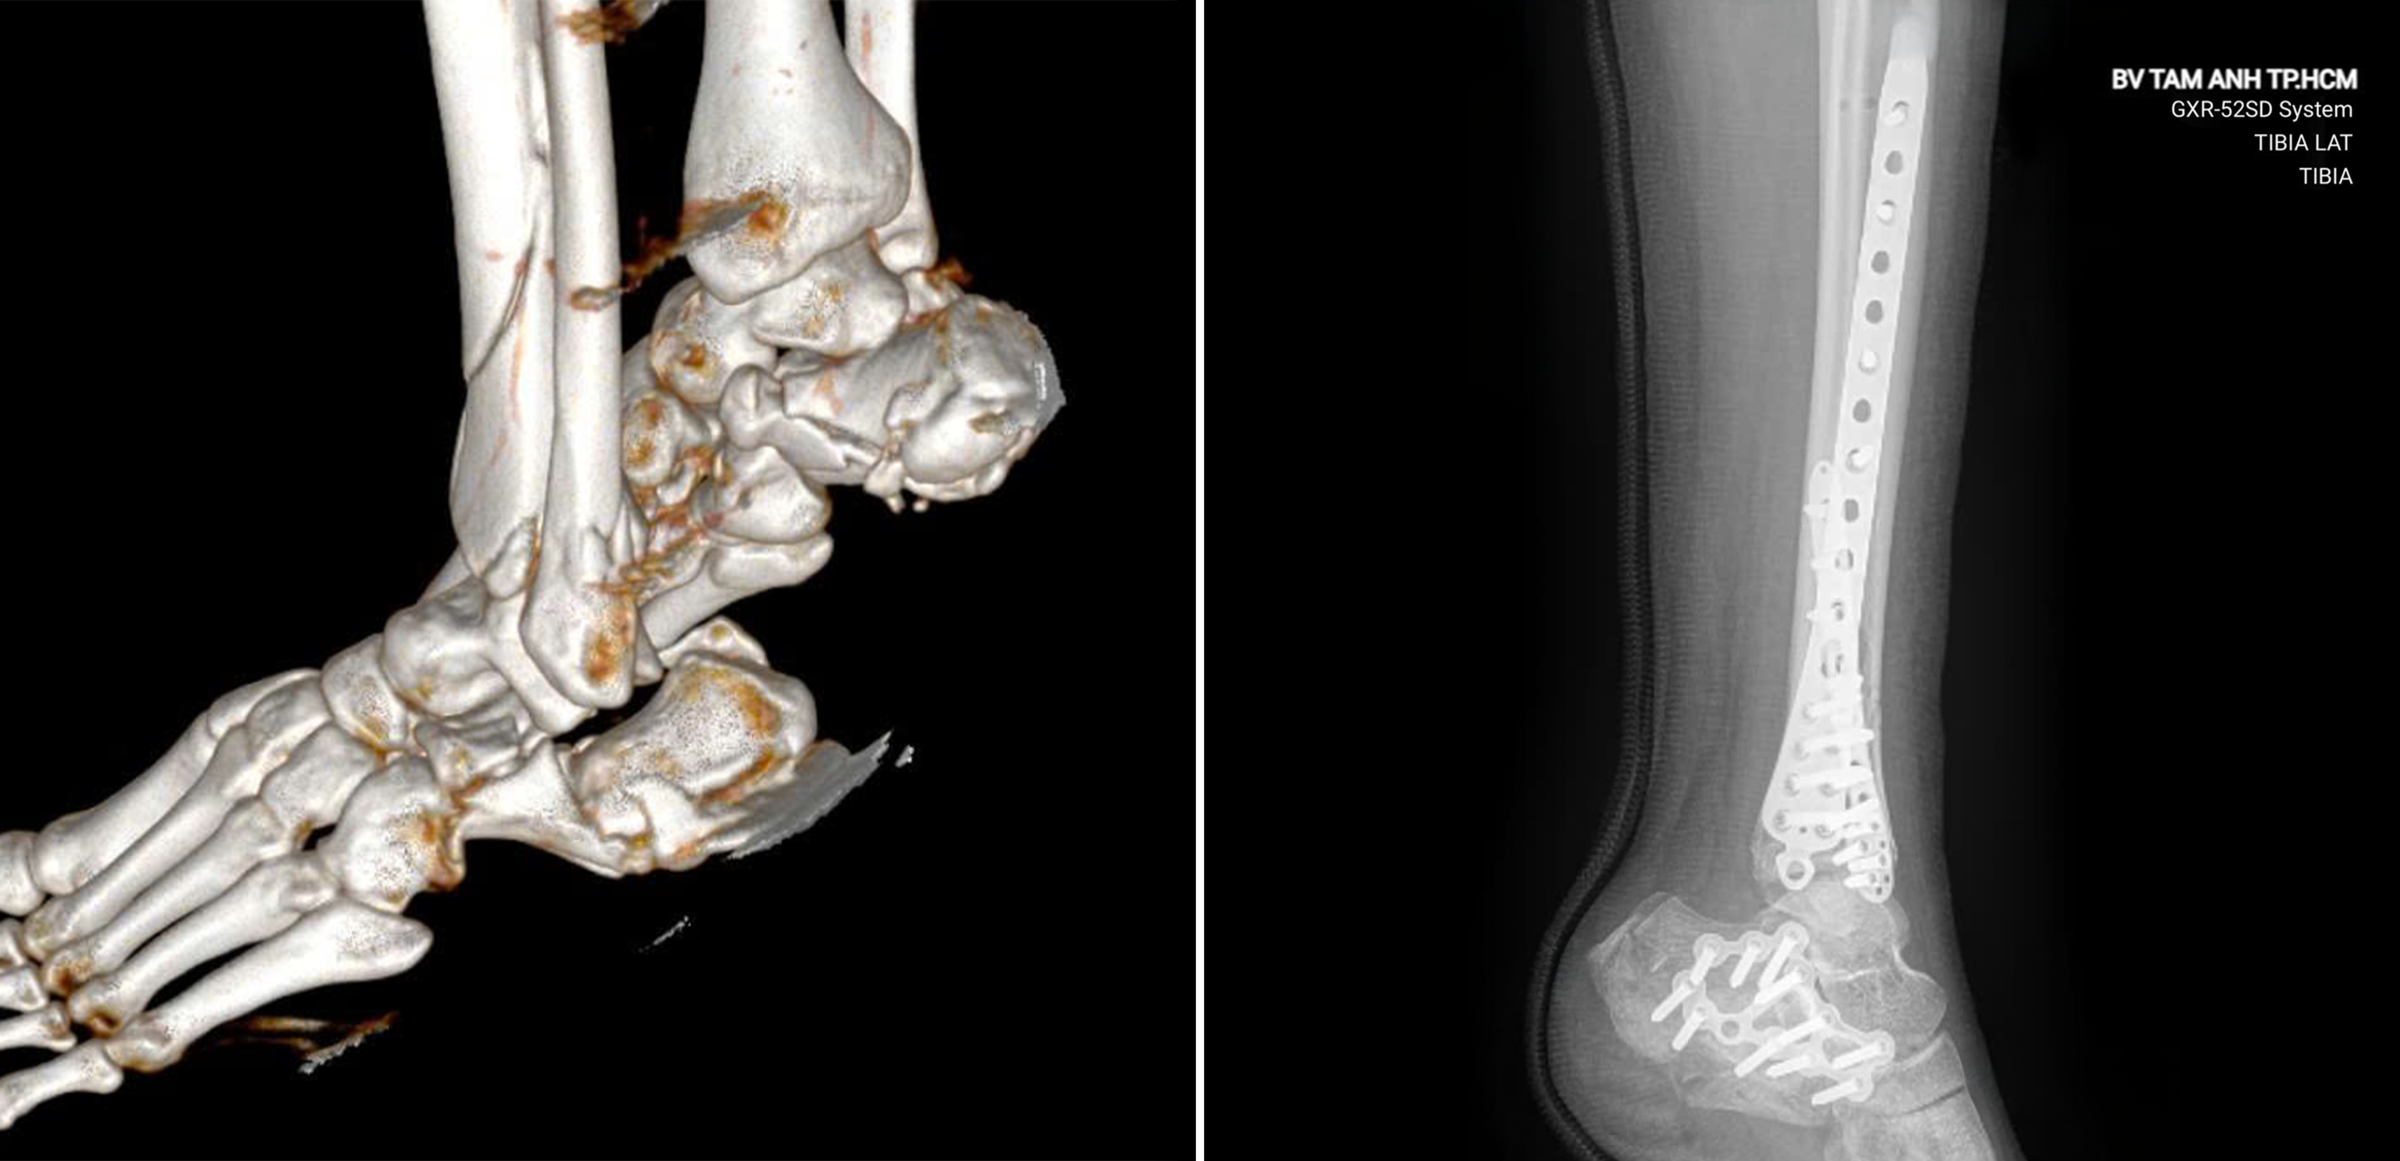

X-rays and CT scans at Tam Anh General Hospital in Ho Chi Minh City revealed that Dara had shattered both heel bones, fractured the lower ends of his left tibia and fibula, and fractured two sacral vertebrae. The soft tissue around the fractures was severely bruised and swollen, with extensive blistering on both feet.

The surgical team used minimally invasive techniques to reduce soft tissue damage and promote faster healing. Small incisions (1-3 cm) were made to insert plates into the tibia and fibula fractures, which were then secured with screws. A C-arm fluoroscopy system was used to ensure precise placement of the hardware.

Due to the complexity of the shattered heel bones and significant bone loss, open surgery was necessary to realign the fragments and perform bone grafting. This aimed to restore the shape and mechanical function of the heels for future mobility. While open surgery provides better visualization and access to the fracture site, it carries a higher risk of soft tissue damage and skin necrosis, demanding meticulous precision from the surgeons.

During the 5-hour operation, the surgeons used 39 screws, 4 plates, and a significant amount of bone graft material. The sacral fractures, which were not affecting function or causing nerve compression, were treated conservatively with observation.

X-rays of Dara's heel before (left) and after surgery. Photo: Tam Anh General Hospital